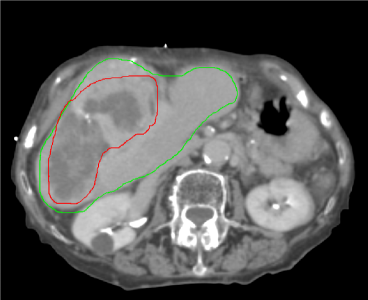

The patient who motivated this work presented with a very large liver tumor (a metastatic lesion originating from chemo-refractory colorectal cancer). The initial target volume in the first treatment stage was assessed using 4D CT, resulting in an internal gross target volume (IGTV) of 1218 cc in size (which incorporated a peak-to-peak motion of 4.15 mm as defined at the fiducials). In comparison, the total volume of normal appearing liver was 870 cc. Thus, the tumor mass accounted for 58% of the total liver volume. The patient was treated in two stages separated temporally by a period of four months. Figure 1 shows the radiotherapy planning CT for the first stage (a) and the second stage (b). Until the most recent follow-up visit (6 months after the second stage), the liver lesion remains stable.

Figure 1: Planning CT image of the patient for the first treatment stage (a) and the second stage (b) four months later. The corresponding CT slices for the two time points are chosen based on the bony anatomy of the spine. The red contour shows the GTV, the green contour corresponds to the liver.

Both treatment stages used a dose painting strategy in which the planning target volume was subdivided into two parts: a low dose PTV was constructed via a 3 mm isotropic expansion of the IGTV; a high dose PTV was constructed by a 1 cm contraction of the low dose PTV. This allowed for a dose reduction to normal radiosensitive tissue adjacent to the target volume while delivering a high SBRT dose to the interior target volume. In the first stage the low dose PTV was treated to 18 Gy in 3 fractions while the high dose PTV was treated to a total of 36 Gy in 3 fractions concurrently. After the four month intermission, the patient returned to be rescanned and treated using the new imaging information. The physician-defined IGTV was 499 cc (37% of total liver volume), and thereby substantially smaller than in the first stage (see figure 1b). The prescribed dose to the low dose PTV for stage two was 20 Gy in 3 fractions, while the high dose PTV received 30 Gy in 3 fractions. Deformable registration was performed in order to assess the cumulative dose to secondary organs at risk, such as the spinal cord and the kidneys. Through the dose painting approach, the mean dose to the non-involved liver (i.e. total liver without GTV) was reduced to 10.8 Gy in the first stage, and 13.3 Gy in the second stage.